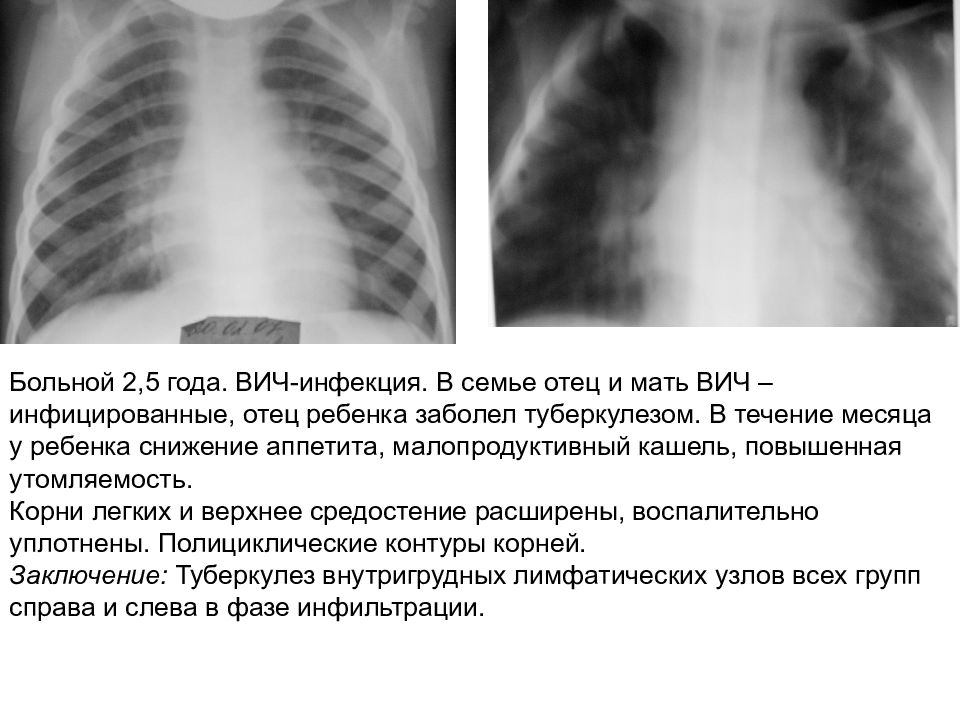

Рентгенологические изображения и синдромы патологии легких

Раздел: Кадры-подсказки